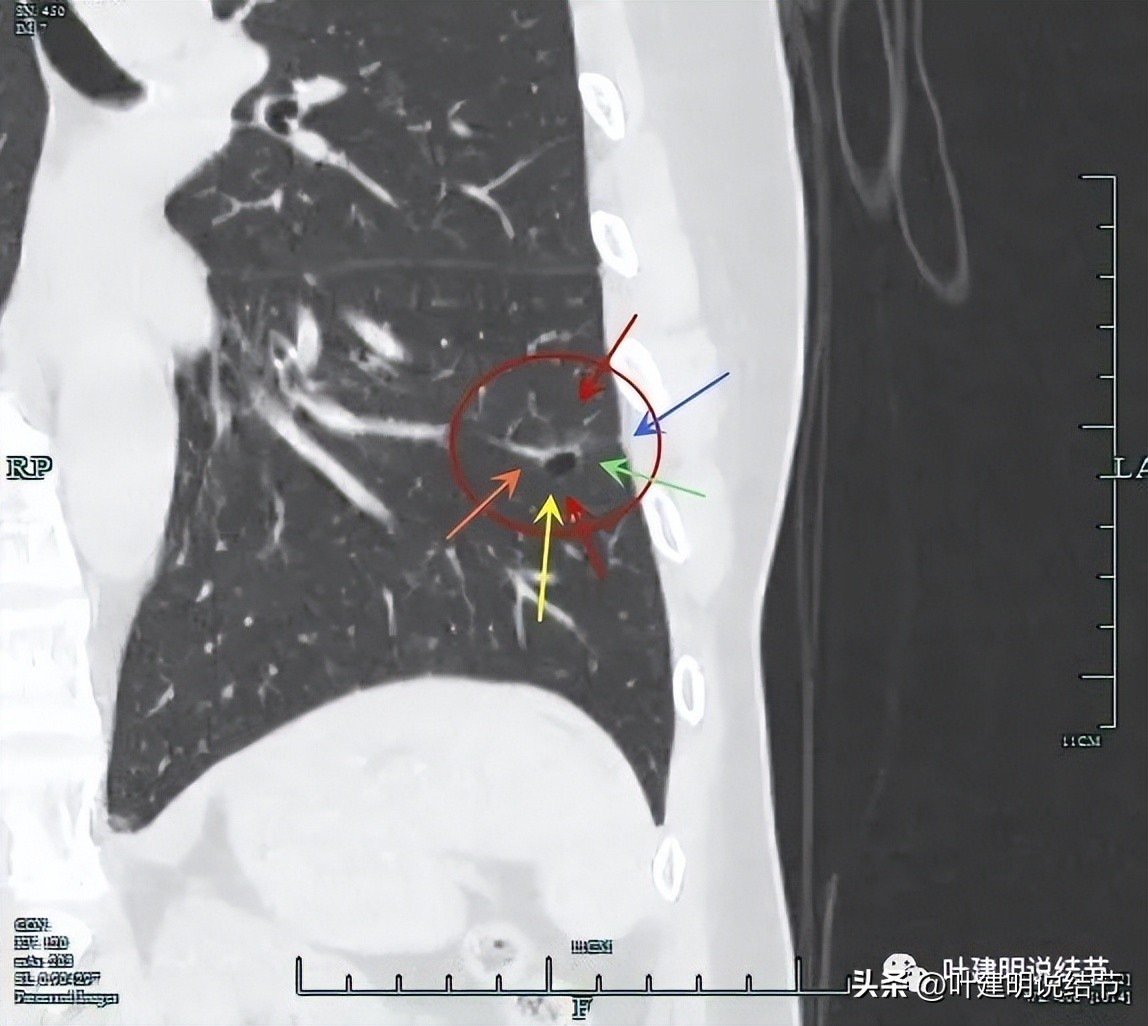

靶重建后发现病灶囊腔型,桔色箭头示进入的血管有异常增粗,而且壁显得毛糙;黄色箭头示空腔;红色箭头示整体轮廓较清;绿色箭头示有磨玻璃成分,虽然密度较低;蓝色箭头示病灶略有胸膜牵拉影响,只是力较弱而已。

显示明显的血管征与血管异常增粗和壁毛糙。

上图显示病灶轮廓较清,有锐利细毛刺征,灶内有弯曲血管穿行。

囊壁有少许是偏实性成分的,如粉色箭头所示。

血管增粗进入并散开来。

血管在病灶内发出分支。